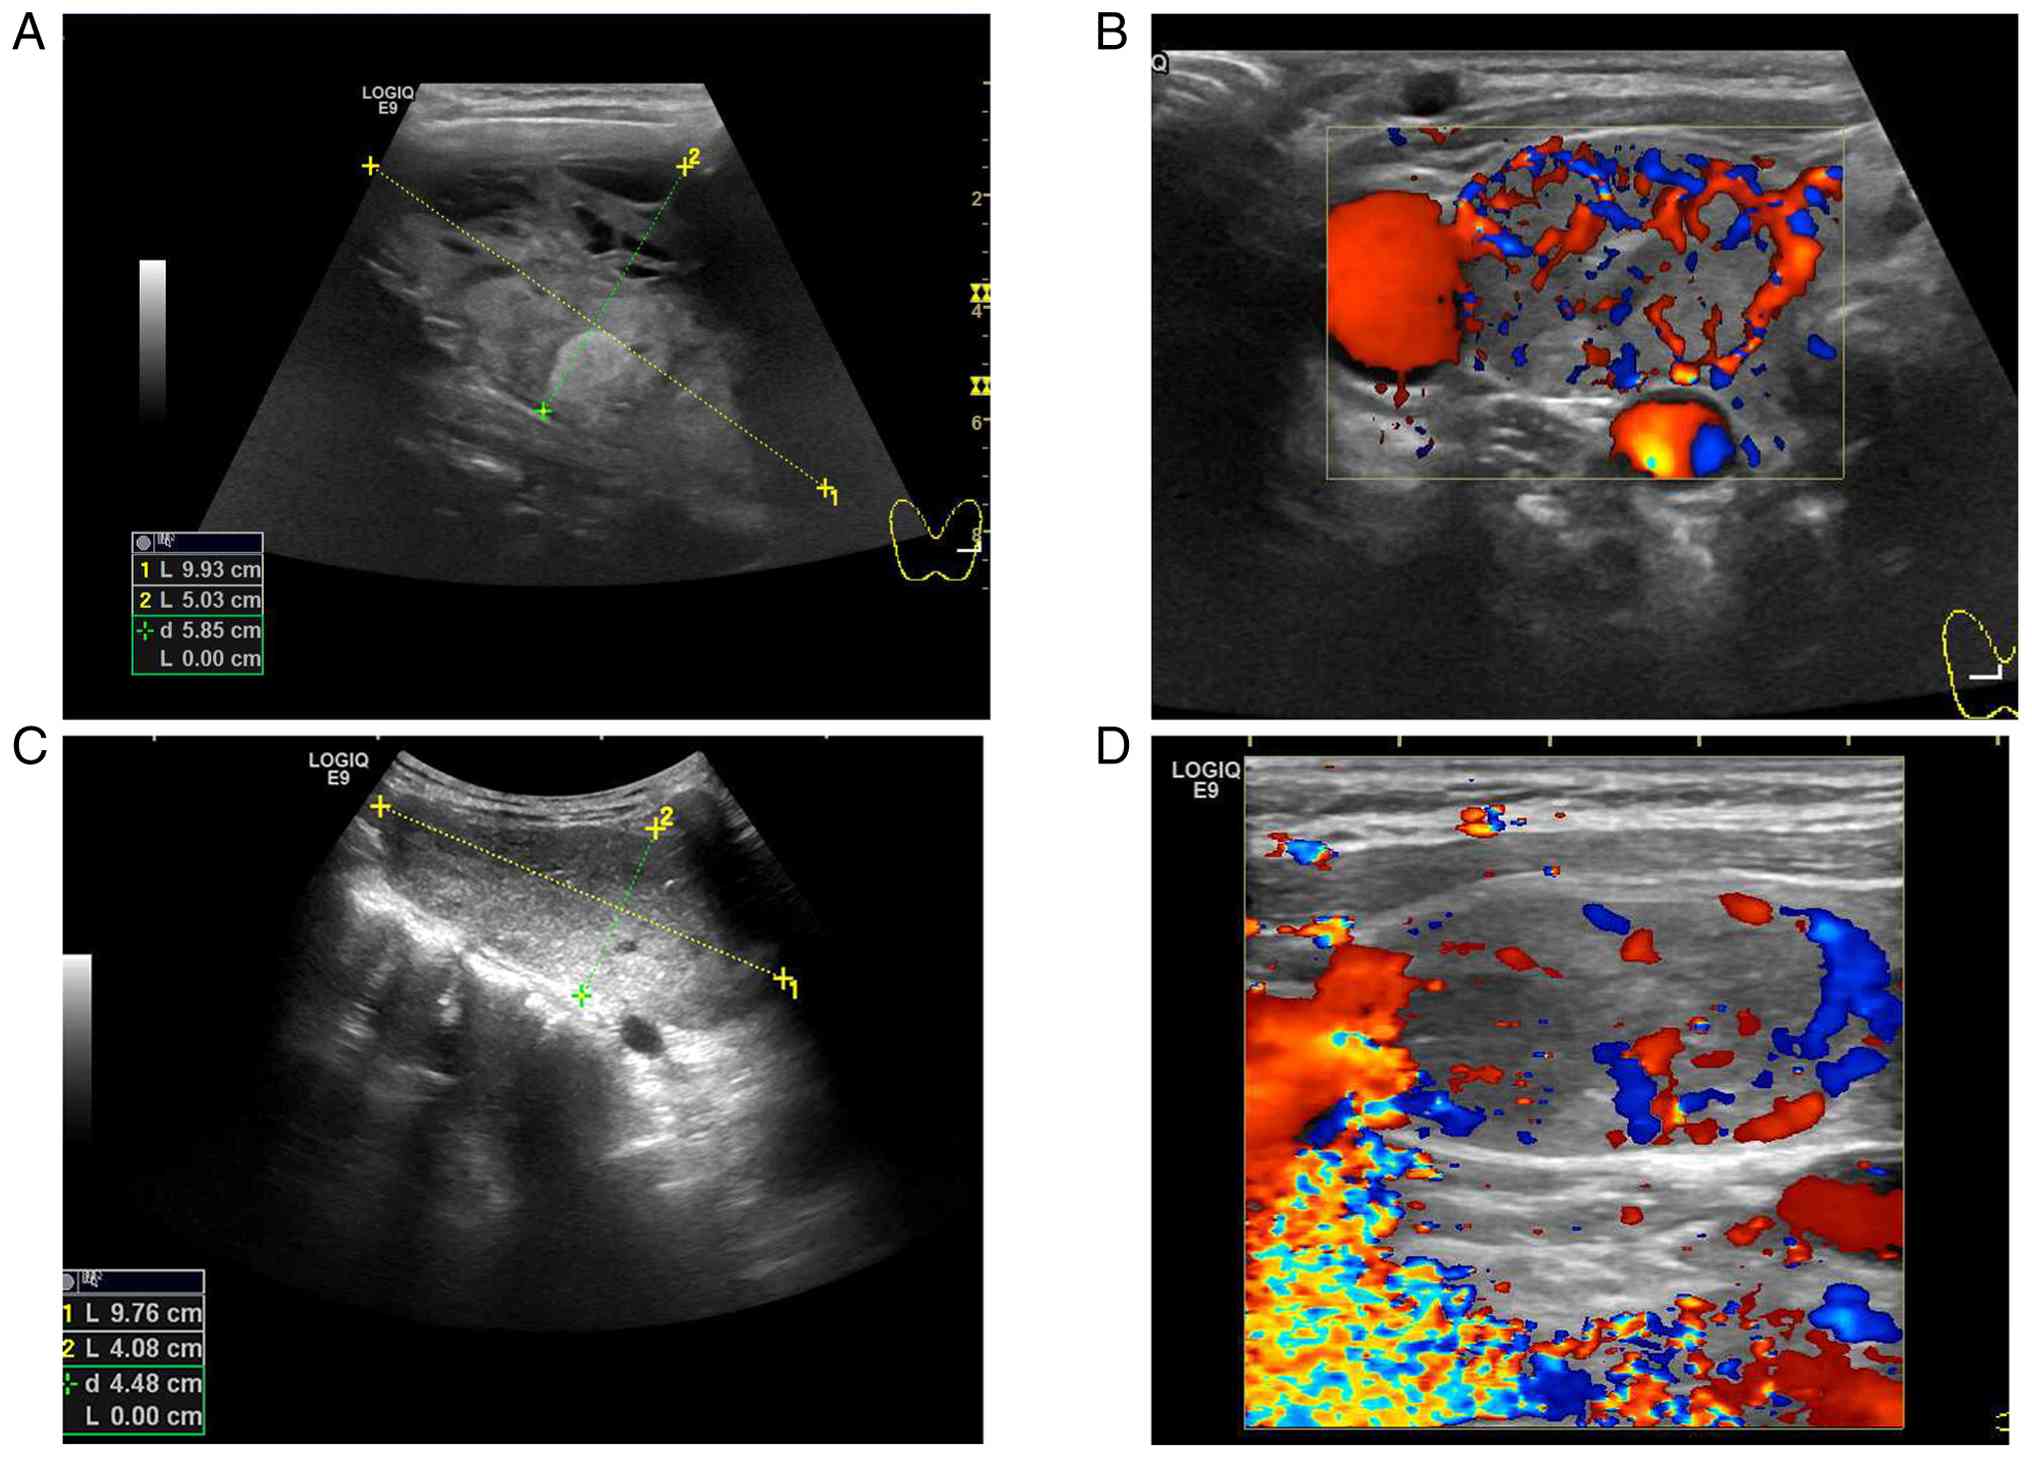

A 70-year-old female patient presented with a goiter that had persisted for 40 years without intervention. Over the past 2 years, the patient had observed an increase in goiter size and experienced dyspnoea while at rest. The patient self-administered Spica Prunellae oral liquid, which was ineffective and was subsequently admitted to the Department of Thyroid Surgery at Weifang People's Hospital (Shandong, China) in March 2025. The patient's arterial oxygen saturation was 92%. Physical examination revealed a well-defined and mobile 5x10 cm mass in the left thyroid gland. It exhibited a smooth surface and showed synchronous movement during swallowing. B-mode ultrasonography identified a complex cystic-solid nodule in the parenchyma of the left thyroid lobe, measuring 99.3x87.3x50.3 mm (Fig. 1A). Color doppler flow imaging revealed extensive vascularization within the lesion (Fig. 1B). CT imaging of the neck and thoracic region demonstrated notable enlargement of the left thyroid lobe, measuring ~7.7x13.0x9.3 cm, with inferior extension into the anterior mediastinum. The mass volume was estimated using the ellipsoid volume formula (V=0.52 x length x width x height), resulting in a value of 484.1 cm3. Imaging findings indicated that tracheal compression leads to a rightward displacement and flattening of the trachea. Quantitative assessment indicated severe tracheal stenosis with a luminal diameter of 4.75 mm (Fig. 2A). Furthermore, the tracheal softening test showed that the trachea moved to the right and was compressed. The inner diameter of the trachea in the Miller's test was 6.06 mm, and the inner diameter of the trachea in the Valsalva test was 11.50 mm (13). (Negative reference value for tracheal softening test: Cross-sectional diameter of the trachea in the ward >7 mm; difference in inner diameter between the Miller's and Valsalva experimental wards <2-3 mm).

(A) Thyroid B-mode ultrasound image of

the patient before thyroid artery embolization showing the mass

with a dimension of 99.3x87.3x50.3 mm. (B) Thyroid color Doppler

ultrasound blood flow signal image before embolization, noting the

marked hypervascularity in the mass. (C) Thyroid B-mode ultrasound

image of the patient after thyroid artery embolization showing the

mass with a dimension of 97.6x40.8 mm. (D) Thyroid color Doppler

ultrasound blood flow signal image after embolization showing that

there is almost no blood flow signal within the mass.

Figure 1

(A) Thyroid B-mode ultrasound image of the patient before thyroid artery embolization showing the mass with a dimension of 99.3x87.3x50.3 mm. (B) Thyroid color Doppler ultrasound blood flow signal image before embolization, noting the marked hypervascularity in the mass. (C) Thyroid B-mode ultrasound image of the patient after thyroid artery embolization showing the mass with a dimension of 97.6x40.8 mm. (D) Thyroid color Doppler ultrasound blood flow signal image after embolization showing that there is almost no blood flow signal within the mass.

The patient underwent comprehensive clinical assessment 3 days after embolization, which included symptomatic evaluation, physical examination and diagnostic imaging analysis. The patient exhibited a notable enhancement in respiratory function, indicating a marked decrease in dyspnoea. Subsequent measurements of oxygen saturation indicated a stable reading of 98%, demonstrating the restoration of normal pulmonary oxygenation status. B-mode ultrasonography revealed a mass in the left thyroid lobe parenchyma (Fig. 1C), measuring 97.6x40.8x87.3 mm in maximal dimensions. The mass exhibited minimal vascularity, indicated by the lack of considerable blood flow signals on Doppler imaging (Fig. 1D). A CT scan of the cervical region indicated that the mass measured 7.6x12.5x9.6 cm, with stable thyroid morphological changes and no notable progression compared with prior imaging studies. The diameter of the trachea at the corresponding anatomical level was measured at 7.54 mm (Fig. 2B). The mass volume was estimated using the ellipsoid volume formula (V=0.52 x length x width x height), resulting in a value of 474.2 cm3. At 1-week post-embolization, the patient underwent a left thyroidectomy. In the surgical procedure, the trachea was carefully suspended on the sternocleidomastoid muscle and anterior cervical muscles to avert the risk of postoperative tracheal collapse. Postoperative monitoring indicated notable enhancement in the symptoms of dyspnoea and choking initially presented by the patient. No instances of hoarseness were observed during the postoperative period. Subsequent laboratory analyses indicated serum calcium levels of 2.25 mmol/l and PTH levels of 64.37 pg/ml, which fell within the normal reference ranges.